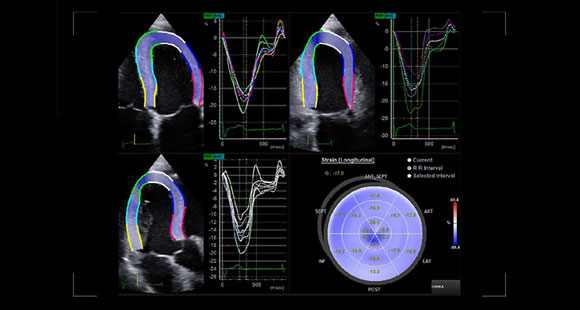

Strain+

Strain + este un instrument care permite efectuarea evaluării cantitative a cineticii parietale globale și segmentare a ventriculului stâng (LV), arătând

trei proiecții standard și o imagine cu patru ecrane „ochi de taur” pentru a vă permite să evaluați rapid și ușor funcția ventriculului stâng.